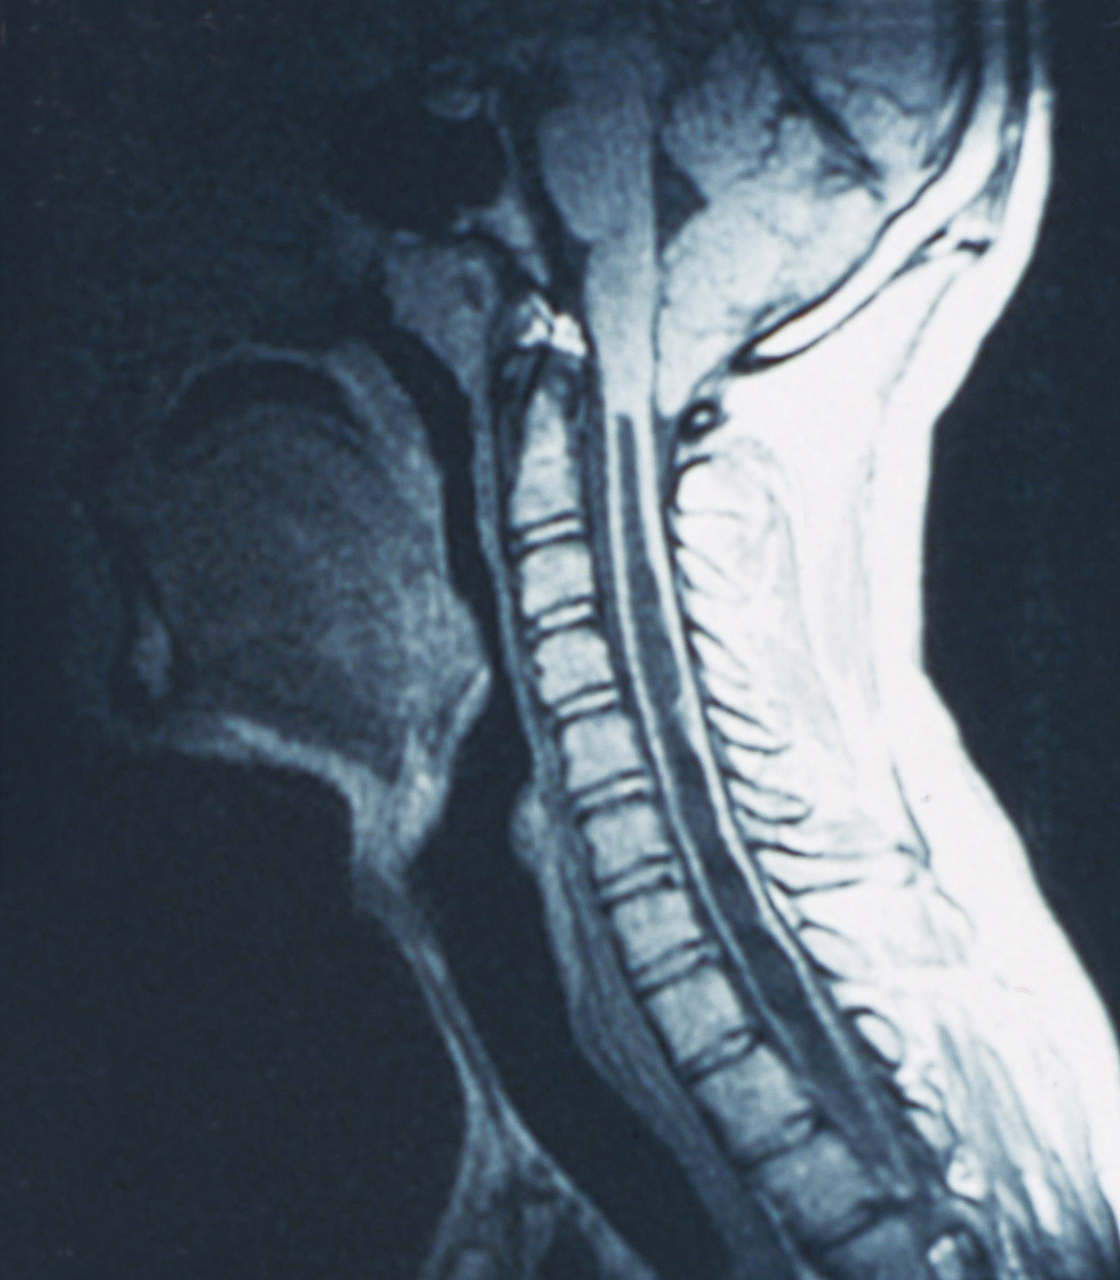

Quel est votre diagnostic ?

Il s'agit d'une syringomyélie. Le diagnostic de syndrome médullaire reste avant tout clinique. Le diagnostic étiologique de syndrome médullaire a été nettement amélioré par la résonance magnétique nucléaire qui permet rapidement d'éliminer une cause compressive et d'orienter l'exploration étiologique. Une fois éliminée une cause compressive, la ponction lombaire garde toute sa place pour compléter l'approche diagnostique. Cela doit aboutir le plus rapidement possible à un traitement, curatif dans certains cas, symptomatique dans les autres cas, notamment en cas de syringomyélie. La syringomyélie est une cavité centromédullaire d'origine malformative ou post-traumatique. La symptomatologie est principalement sensitive, thermo-algique, suspendue, par lésion des fibres spinothalamiques centromédullaires. Une atteinte motrice est plus inconstante, témoignant d'une extension de la cavité vers la corne antérieure médullaire, et se manifeste par une amyotrophie et une abolition des réflexes ostéotendineux dans le territoire concerné.